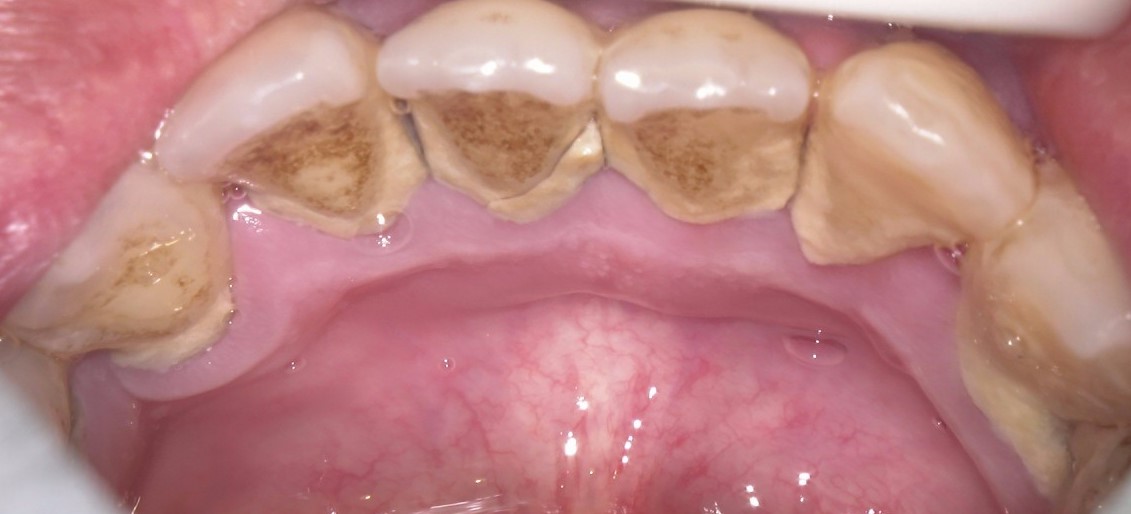

歯についた着色ってどうやっておとすの?

歯についた着色気になりますよね?俗にいうヤニとかは歯科医院の専門的な器具でとることができます。 それは何を使ってとっていくかというとエアフローというものです。 エアフローは、高速の空気と水の噴射によって、歯の表面からプラ […]